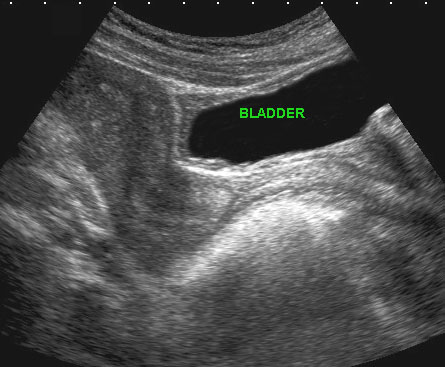

Các hình ảnh này của một phụ nữ trẻ bệnh nặng, đau nhiều với viêm phúc mạc toàn thể và CRP 250, nghi ngờ lâm sàng là thủng ruột thừa.

Siêu âm cho thấy ruột non mất nhu động (b.).

Không quan sát được ruột thừa.

TVUS cho thấy tử cung bình thường và buồng trứng bình thường (đầu mũi tên), được bao quanh bởi mô tăng âm (*).

CT xác nhận hình ảnh liệt ruột và ruột thừa bình thường (mũi tên).

PCR dương tính với lậu cầu.